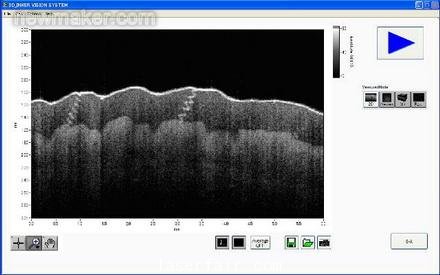

圖1. Santec公司的 便攜式OCT係統使 用基於(yu) FPGA的圖 像處理

我們(men) 的係統現在可以更快地顯示物體(ti) (包括人體(ti) 器官和其他移動的樣品)的圖像。而且,新的基於(yu) FPGA的係統可以提供實時測量信號處理,通過消除測量和顯示之間的延遲,提高顯示性能。圖4表示成像係統的LabVIEW麵板。

圖4. SS- OCT成像係統的麵板